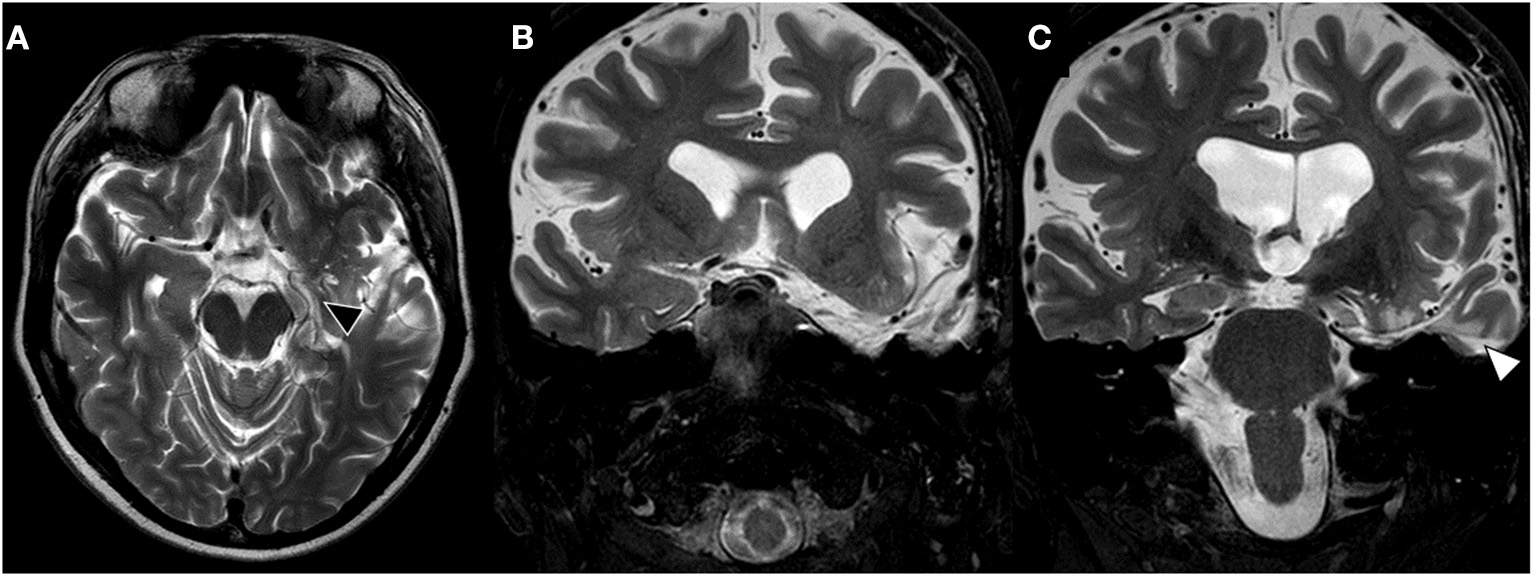

Figure 2

Late post-surgical brain MRI. (A) T2-weighted axial brain MRI shows left hippocampus resection (black triangle). (B, C) Coronal brain images showing complete resection of left amygdala and uncus on image (B) and hippocampal resection through transcortical approach (T2, white triangle).